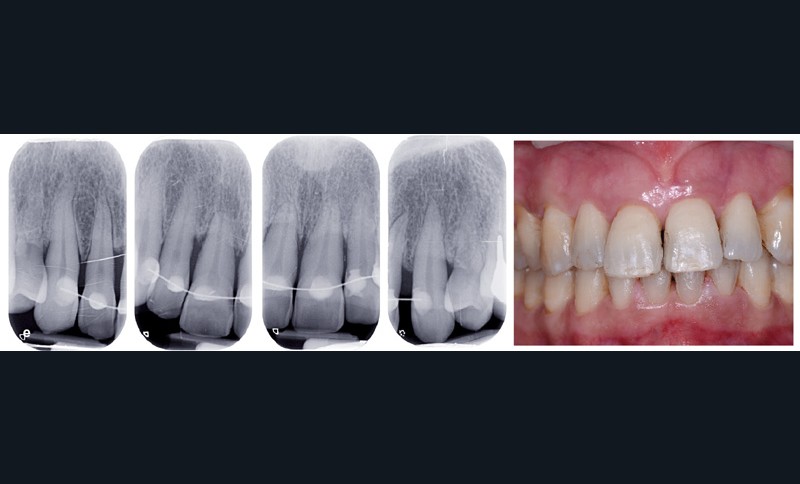

Bien souvent, dans les formes sévères, la diminution du boîtier osseux entraîne la migration et le déplacement de dents et notamment dans le secteur antérieur. Ces migrations ont un aspect disgracieux qui amène bon nombre de patients à consulter un orthodontiste pour corriger ces malpositions et retrouver à la fois une esthétique du sourire plus agréable et une fonction masticatrice plus efficace. Cependant, l’origine de ces migrations tient à l’inflammation du parodonte se traduisant par une plus grande laxité ligamentaire et une destruction du boîtier osseux. Dans certains cas, une surcharge occlusale aggrave encore le déplacement. Le traitement de l’inflammation par une thérapeutique initiale parodontale diminue la migration mais souvent, ne suffit pas à retrouver un positionnement correct (fig. 1). Il est alors nécessaire de mettre en œuvre une prise en charge orthodontique.